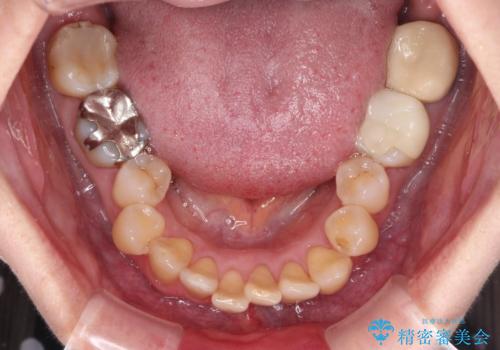

- 上下前歯のデコボコと、奥歯の銀歯を気にして来院された患者様です。

概ね歯列が整ったところで銀歯の全てをセラミッククラウンなどに置き換え、その後インビザラインを1セット使用して仕上げていくこととしました。